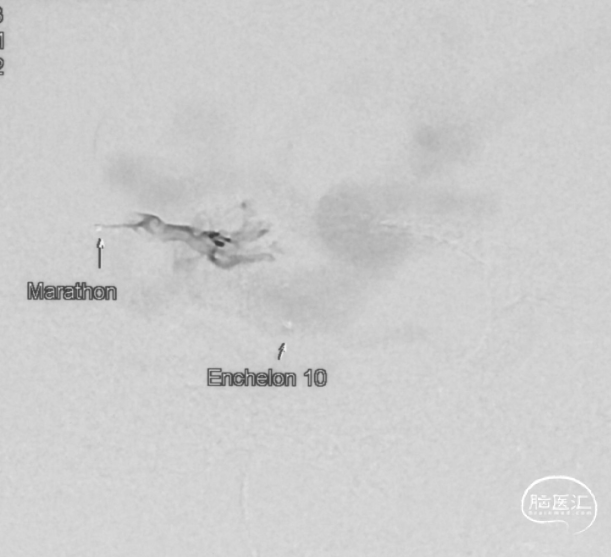

选取工作角度,正侧位造影

Echelon-10微导管在ASAHI 0.010微导丝导引下经右侧脑膜中动脉分支超选至瘘口,可见瘘口口径大,微导管直接越过瘘口,进入引流静脉起始部。

Marathon微导管在ASAHI 0.010微导丝导引下经右侧脑膜中动脉分支超选至瘘口近端。

经Marathon微导管手推造影明确微导管位于瘘口动脉端,Echelon-10微导管位于瘘口引流静脉起始端处扩张的静脉球内。